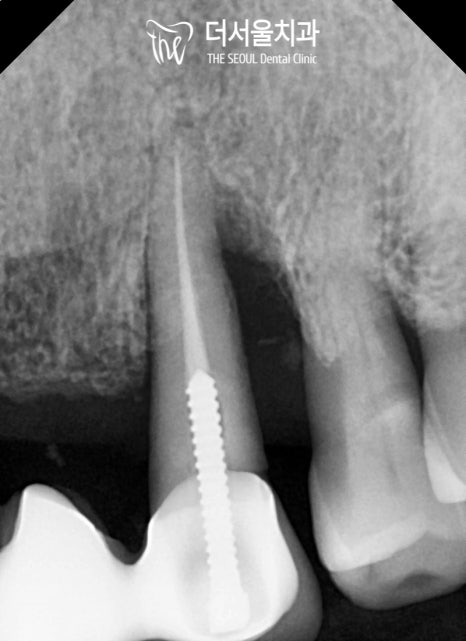

실제 구강 내를 본을 뜬 다음

인접치, 해부학적 조직과의 모든 관계를

꼼꼼히 파악해주는 똑똑한 친구입니다.

3차원으로 분석을 마친 뒤에는

제작된 가이드를 사용하여 식립을 마쳤습니다.